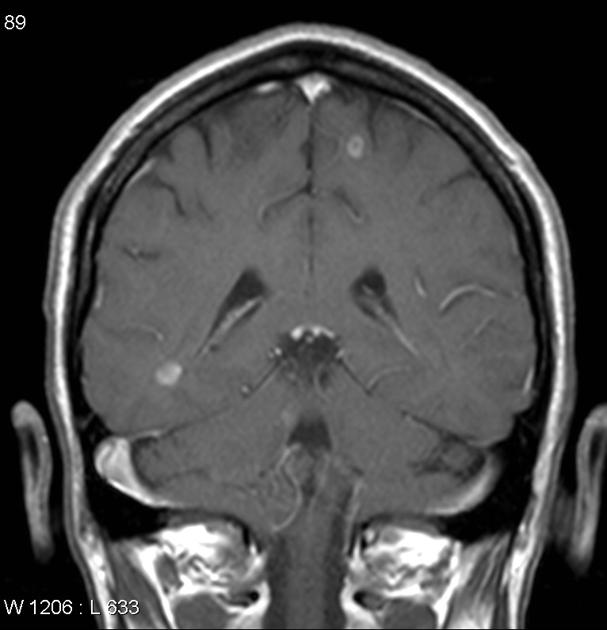

На Т2-взвешенных изображениях визуализируются участки гиперинтенсивного сигнала в веществе мозга, чаще в глубинных структурах, что соответствует зонам периваскулярного инфильтрата.

В режиме с контрастированием определяется интенсивное усиление сигнала от менингеальных оболочек, гипофиза, ствола мозга и черепных нервов, что характерно для активного течения нейросаркоидоза.

- Очаги гиперинтенсивного сигнала в глубинных структурах на Т2-взвешенных изображениях указывают на вовлечение периваскулярного пространства.